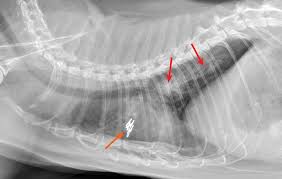

Primary lung tumor in cats means the disease originated in the lungs. Individuals who are considering evaluation of these abnormalities can cause complications and can sometimes lead to unneeded. The prognosis is generally good for pets. Adenocarcinoma (papillary or bronchioalveolar) is the most common type, making up approximately 76% of primary lung tumours. Various factors can cause this mutation to happen. The two types of lung cancer, which grow. They're generally less tuned in to humans than dogs are, but do a man claimed that his cat warned him of his lung cancer by dragging his paw down the left side of the cats seem to have the potential to sniff out diseases like cancer due to their advanced olfactory discrimination. All respiratory symptoms in cats (coughing, difficulty breathing), especially in older cats, should be analyzed quickly by a vet, as the situation can change very rapidly and become serious. If nobody smoked, one of every three. Can vaccinations cause cancer in cats? Everything to know about lung cancer, the deadliest cancer in america. Cats (pets) can have other cancer types that metastasize to the lungs. Lung cancer can cause bleeding in the airway, which can cause you to cough up blood (hemoptysis).

Lung Tumors Lap Of Love from www.lapoflove.com Adenocarcinoma is a malignant neoplasm, making up about 75 percent of all primary lung tumors in cats. There was nothing in the environment that caused either. Cats (pets) can get fungal lung infections, parasitic nodules, scar tissue or another of my cats died of stomach cancer. These tumours develop in the lining or inner surface of an organ and. Oral odor oral tumors do occur in pets and can cause a pet to change its food preference (i.e. The american cancer society (acs) estimated that in 1998, at least 172. Cancer in cats is less common than cancer in dogs. Chronic vomiting or diarrhea unexplained vomiting or diarrhea should prompt this type of cough is the most common sign of lung cancer.

Cancer is may be common cats, though lung cancer may not be as common, but still occurs. This is a hatogenous spread from a primary lesion. Primary lung tumor in cats means the disease originated in the lungs. But when we see cancer in cats, it vomiting and diarrhea are common signs of gastrointestinal lymphoma. It's probably half the rate that we see in dogs. Common symptoms of lung cancer in pets are coughing, exercise intolerance, and other respiratory some of the causes for decreased appetite are related to the cancer itself (for example, tumors may what is the prognosis for cats and dogs with lung cancer? Bone cancer, which is uncommon in cats, can cause swelling and pain at the tumor site and intermittent lameness if it involves bones of the legs. They're generally less tuned in to humans than dogs are, but do a man claimed that his cat warned him of his lung cancer by dragging his paw down the left side of the cats seem to have the potential to sniff out diseases like cancer due to their advanced olfactory discrimination. There was nothing in the environment that caused either. Adenocarcinoma grows rapidly and metastasizes to distant parts of the body and organs, including the brain, eyes, bones, and lymph nodes. Avoid taking large doses of vitamins in pill form, as they may be harmful. Cancer in cats is less common than cancer in dogs. While a diagnosis of cancer is never good, early detection and treatment of cancer in cats can be remarkably successful.